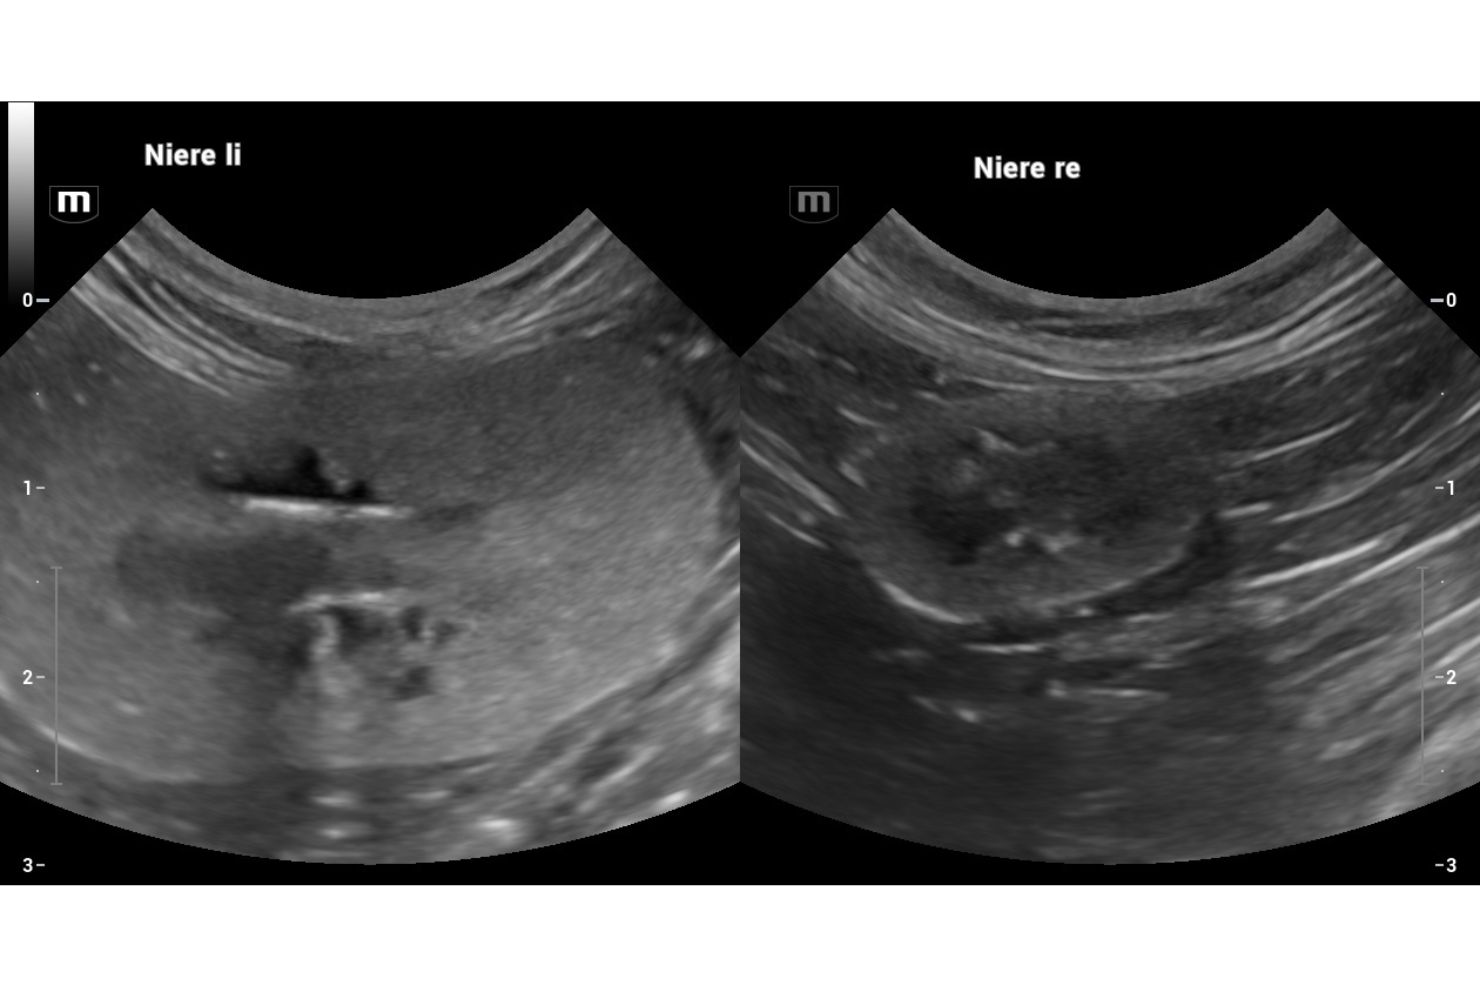

Fortgeschrittene strukturelle Veränderungen zeigen sich bei Katzen durch eine fleckige, hochgradige Hyperechogenität, meist verbunden mit einer anfänglichen Schwellung der Nierenrinde. Es ist keine Unterscheidung der Rinden-Mark-Grenze mehr sichtbar; das Nierenbecken ist erweitert. Daran können wir erkennen, dass diese Niere definitiv schon längere Zeit ein Problem hat. Wenn auch radiäre, hyperechogene Streifen sichtbar sind, ist das prognostisch besonders ungünstig. Eine Verdickung der Nierenrinde ist sowohl bei Hunden als auch bei Katzen ein Alarmsignal – eine Niere, die bereits länger schlechter arbeitet, wird kleiner und höckrig. In weiterer Folge erscheint dann auch das Nierenbecken geringgradig dilatiert. Hier hilft es, beide Nieren zu vergleichen. Die Messung der Breite des Nierenbeckens sollte allerdings nur im Querschnitt erfolgen.

Größere Konkremente in der Niere sehe ich vergleichsweise selten. Was die Hydronephrose betrifft, so gibt es leider in der Veterinärmedizin keine Klassifikation der verschiedenen Stadien; die Humanmedizin hat im Gegensatz dazu viel genauere Kriterien festgelegt. Meiner Erfahrung nach kann sich eine etwaige Hydronephrose nach chirurgischer Intervention wieder erholen, wenn etwa eine Obstruktion durch ein Konkrement im Ureter vorlag, solange noch eine Rinden-Mark-Grenze beziehungsweise größere Anteile der Rinde vorhanden sind.